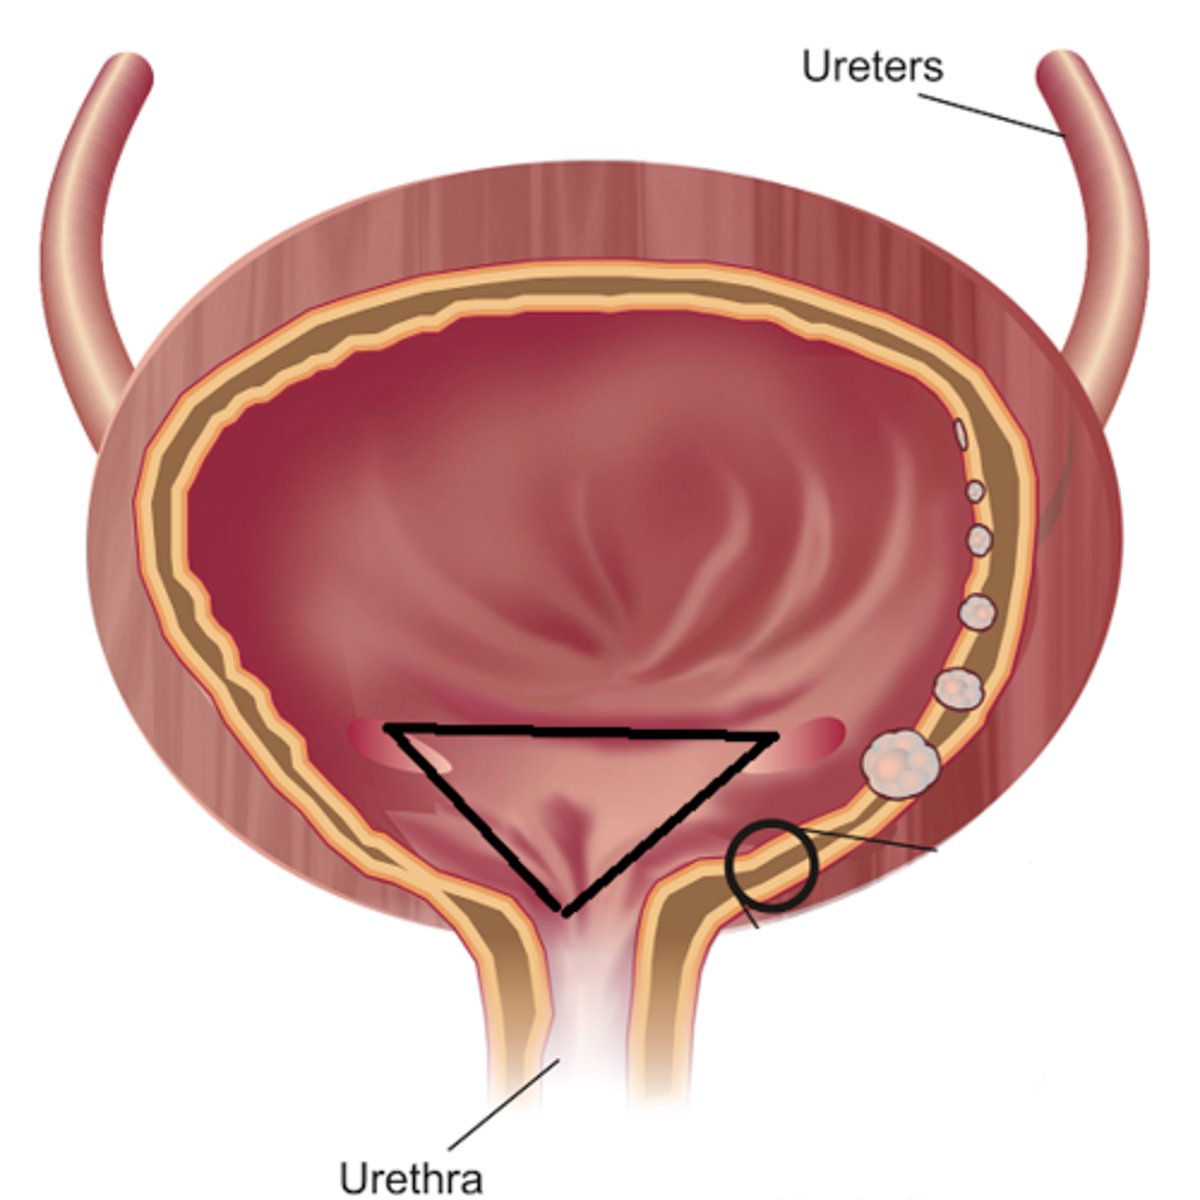

urinary bladder

urinary bladder

detrusor muscle

layer

internal urethral sphincter

bladder neck

external urethral sphincter

ureteric orifice

trigone of bladder

rugae

Urethra